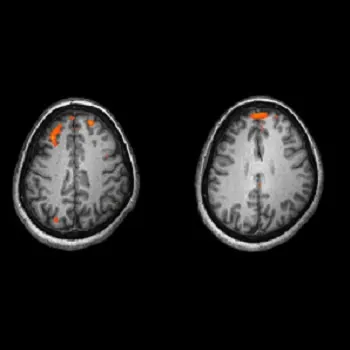

Symptoms of schizophrenia can be partly explained by disordered connectivity in the brain. It is already known that brains of schizophrenia patients are wired differently and work less efficiently. The scientists used a specific type of MRI that maps the wiring of the brain to identify how the brains of young people who have some symptoms of schizophrenia are wired differently.

They scanned 123 people who have vulnerability to psychosis, and 125 people without vulnerability and compared the differences in the wiring of their brains. The findings showed that in people who were vulnerable to schizophrenia, the ability of the brain network to transmit information from one region to another was reduced and some information pathways were rerouted. This affected certain  information hubs of the brain leading to widespread problems in information processing that is similar to schizophrenia.

Cardiff University’s Dr Mark Drakesmith, who led the research, said: “The changes we’ve identified in the brain networks are extremely subtle. However, using a specific type of Magnetic Resonance Imaging (MRI) which maps the wiring of the brain, we have made some key discoveries that would not have been detected using more established brain imaging techniques. The technique employs a branch of mathematics called ‘graph theory’, which allows us to examine complex architectural features of networks, such as efficiency of information transfer. This approach is traditionally used in computer science, but is now giving neuroscientists and psychiatrists new insights into how configurations of brain networks are altered in mental illness.“